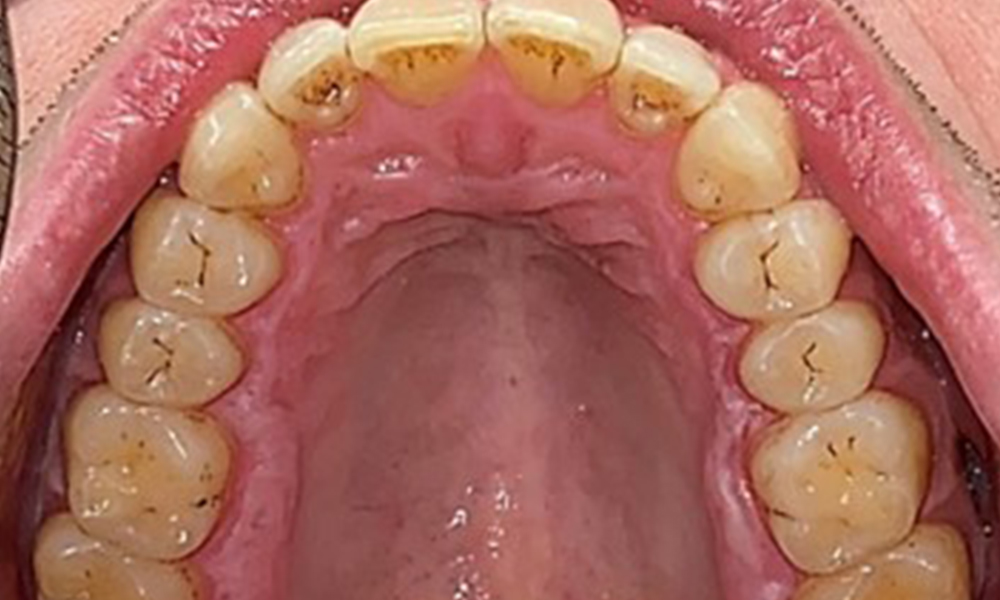

Occlusal view of the maxilla.

Fig. 3: Occlusal view of the maxilla, © Dr R. Krapf

There were no pathological extraoral findings. During intraoral examination, inspection of the frontal view revealed brownish discolouration near the keratinised gingiva and at the transition to the moveable mucosa (Fig. 2), which could be attributed to nicotine consumption. Whitish mucosal lesions were observed on the palate, particularly near the maxillary molar palatal surfaces, indicating increased keratinisation and can also be attributed to nicotine consumption. The tongue was covered with a removable white and brownish coating.

The patient has full dentition with a total of 28 teeth. There were noteworthy erosions and attritions. (Fig. 4, Fig. 5). Due to bruxism, the patient has been wearing a splint with an adjusted bite block at night for many years. The erosions were caused by long-term consumption of isotonic beverages. No periodontal bone loss or active caries were observed.

Full complement of adult teeth with no caries or radiologically recognizable bone loss was observed (Fig. 6). Radiological enamel and cusp loss were particularly evident on 36 and 37.